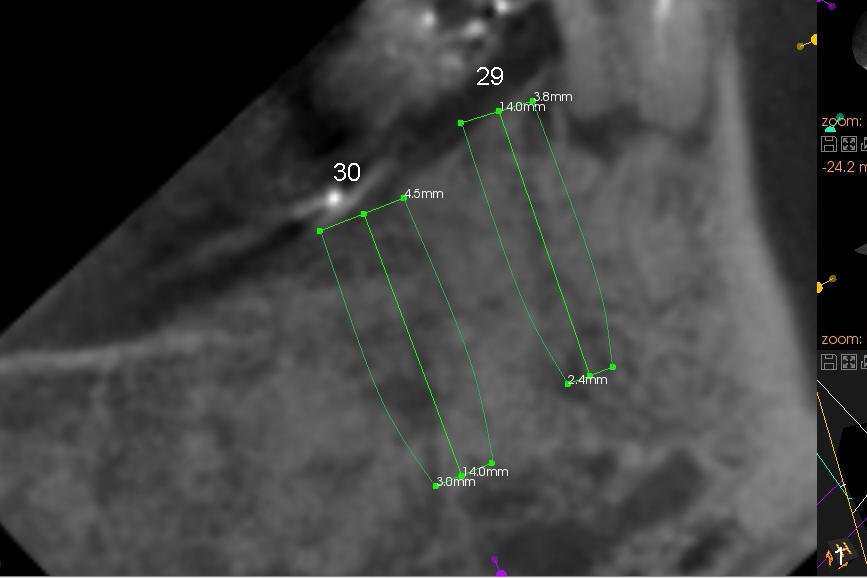

A 85-year-old man has poor dentition (Fig.9). Multiple implants are to be placed at one or two stages (#26-30). If primary stability is obtained for individual implants, they are splinted and immediate provisional is fabricated.

Fig.1-3 are CBCT sagittal sections of the lower right quadrant, whereas Fig.4-8 are coronal sections. The lower left quadrant has been restored.